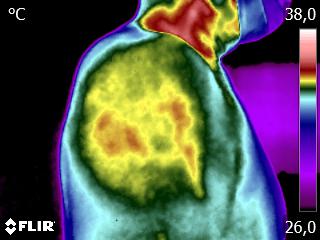

Como no caso do termograma abaixo de um paciente do sexo masculino, 52 anos, sem comorbidades e que apresenta dor em ombro após treino de musculação. Foi realizado uma Análise Termofuncional e detectado alterações térmicas condizentes com o relato de dor.

Segundo os conhecimentos da Termofuncional, estes resultados representam sobrecarga tecidual, podendo estar ligada a biomecânica errada. Através destes conhecimentos é possível o terapeuta partir para uma análise focada na biomecânica e na carga de treinamento, corrigindo ambas.

Além, claro, de permitir um mapa para escolhas de tratamento através de métodos e técnicas terapêuticas que o profissional achar adequado. Ao longo da reabilitação, também é possível o profissional monitorar os resultados alcançados para aumento da eficácia do tratamento.

Tudo isso também permite o registro documental que é a sua segurança e a do paciente. Nenhuma outra técnica permite, de forma autônoma, um registro documental tão preciso como este.